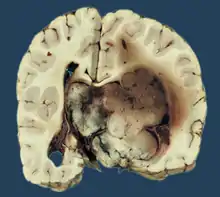

Choroid plexus papilloma, also known as papilloma of the choroid plexus, is a rare benign neuroepithelial intraventricular WHO grade I lesion found in the choroid plexus.[1] It leads to increased cerebrospinal fluid production, thus causing increased intracranial pressure and hydrocephalus.[2]

Choroid plexus papilloma occurs in the lateral ventricles of children and in the fourth ventricle of adults. This is unlike most other pediatric tumors and adult tumors, in which the locations of the tumors is reversed. In children, brain tumors are usually found in the infratentorial region and in adults, brain tumors are usually found in the supratentorial space. The relationship is reversed for choroid plexus papillomas.

Choroid plexus tumors are divided into three categories by the World Health Organization (2016):[9] papillomas (grade I), atypical tumors (grade II), and carcinomas (grade III). Less than two mitotic figures per 10 high power fields are present in CPPs, two to five are present in atypical ones, and more than five are present in carcinomas. The tumors are visible as pink, soft, spherical lumps with erratic projections and considerable vascularity.